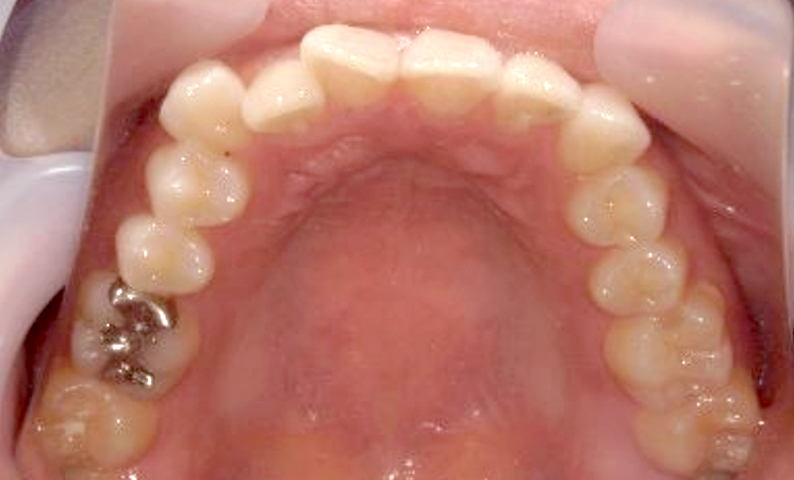

症例_018 上顎だけの部分矯正

治療期間:7ヶ月金額:30万円+税女性前歯のガタガタ上の前歯だけ

| Before | After |

|---|---|

|